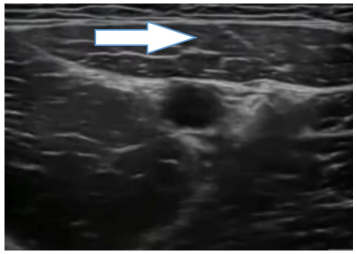

O bloqueio anestésico do ramo femural é facilmente realizado ao nível do canal dos adutores. Esse bloqueio é bastante utilizado para

procedimentos realizados abaixo do joelho. Como referência principal para realização do bloqueio, identifique a estrutura apontada

pela seta presente na imagem.